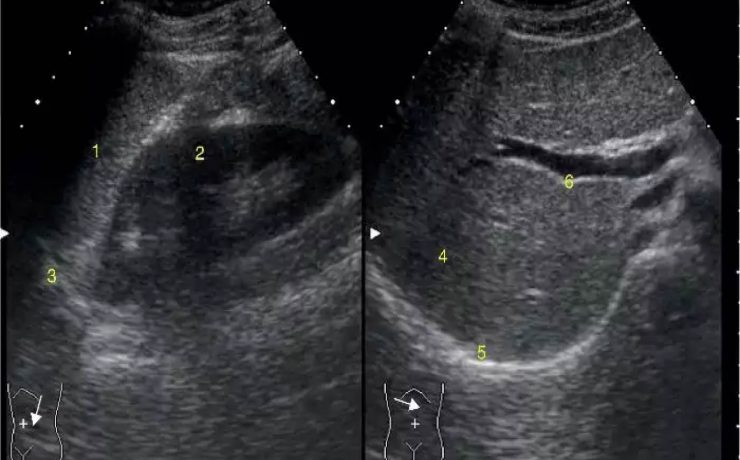

El objetivo del presente artículo es demostrar que la medición ecográfica del cordón umbilical es un factor que puede predecir la macrosomia fetal. Para lo cual se llevo a cabo un estudio descriptivo, observacional en mujeres gestantes a término cuyos factores de inclusión fueron gesta de 37 semanas, producto único